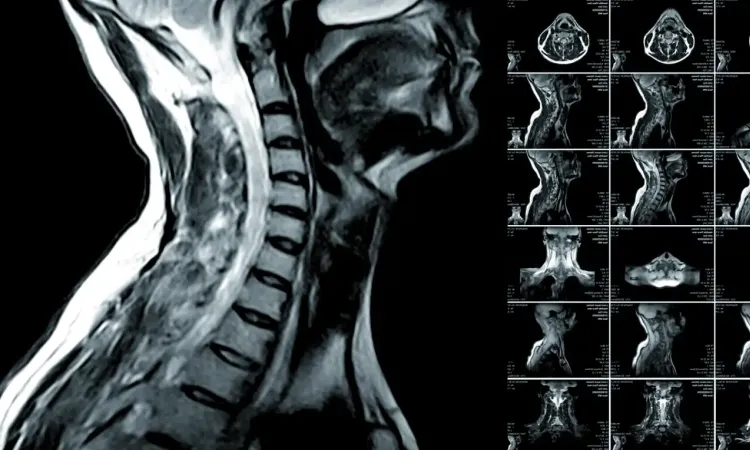

МРТ шейного отдела позвоночника

Магнитно-резонансная томография — высокоинформативный метод, позволяющий детально исследовать каждый структурный компонент: шейные позвонки, связочный аппарат, расположенные рядом мягкие ткани и спинной мозг.